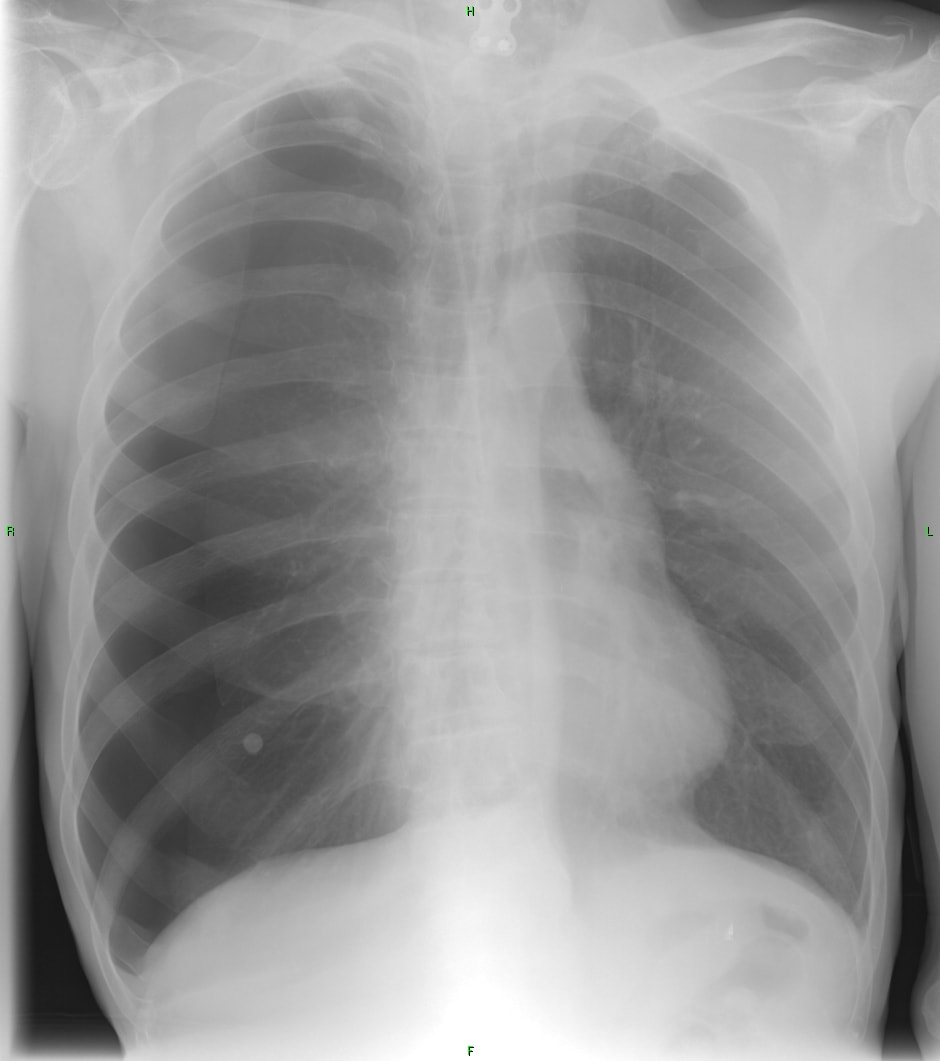

The lateral view confirms the presence of a retrocardiac mass with an air-fluid level. There is also aortic uncoiling with atherosclerotic calcification of the arch and descending aorta.

Diagnosis: Hiatal hernia.

This case is a classic example of the hiatal hernia seen on chest x-ray. A hiatal hernia is a herniation of the stomach through the esophageal hiatus of the diaphragm, usually involving the fundus of the stomach. There are 2 main types of hiatus hernia which are differentiated on the location of the gastroesophageal junction :

a. sliding - most common type, junction displaced upwards into mediastinum (ie behind the heart shadow), often small and reducible

b. paraesophageal/rolling - least common, junction lies normally below the diaphragm, may not reduce

A hiatal hernia may be clinically silent and only discovered incidentally. When symptomatic the signs are usually nonspecific such as dull chest pain, shortness of breath, in some cases heart palpitations, nausea, or signs of acid reflux such as heartburn and belching.

Hiatal hernias are more common with increasing age and in smokers and obese individuals. Potential causes include weakness in the diaphragm, either congenital or trauma related, or persistent intense stress on the adjacent musculature such as produced by severe cough, vomiting, lifting heavy objects, or excessive straining with bowel movements.

Dietary changes (avoiding foods that cause heartburn, avoid alcohol) and lifestyle changes (sleeping in an elevated position, cessation of smoking) can help lessen the symptoms of acid reflux related to the hernia. Laproscopic surgical repair may be performed in cases of large sliding hernias, paraesophageal type hernias, or if there are signs of acid reflux.